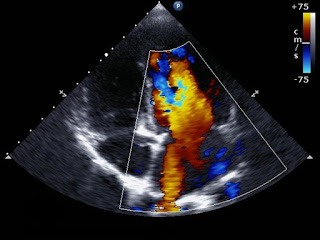

| Echocardiogram Image |

Unlike the ultrasound machine, the echocardiogram was full of color, at least a few colors. This marvel of modern science is able to show blood flow through the heart as well as any defects using high frequency sound waves. The machine also measures oxygenated and deoxygenated blood using blue and red imaging. In my mind, this is how the ultrasound machines should display their findings; brilliant, beautiful, pulsating colors full of life.

We choked back tears and gave a little laugh. We watched as red and blue colors raced across the screen and disappeared. There it was, in living color, the heart of our daughter. Although I was not a trained physician, even I could tell something strange was going on. The heart was beating rhythmically. Blue and red blood rushed in and out of the heart. Yet every so often the heart would pulse or jump. The blue and red appeared to mix and then just as quickly all went back to normal. Nicole and I both saw it. She knew exactly what was going on deep in her womb, deep beneath flesh and fluid, blood and water, deep in the tiny heart of the tiny baby so many other hearts and minds were praying for at that very moment. The nurse saw and understood. Nicole saw, felt, and understood. I was an outsider, a guilty bystander in a world of women. A stranger among nurses who communicated with smiles, nods, and knowing glances.